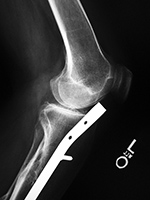

Left tibia stress fracture after fibular fracture fixation |

A short one-third tubular plate and screws plus interfragmentary screw stabilize a healing distal fibular fracture. An associated stress fracture (arrow) is in the distal tibial metaphysis from altered weight-bearing from the fibular fracture. |